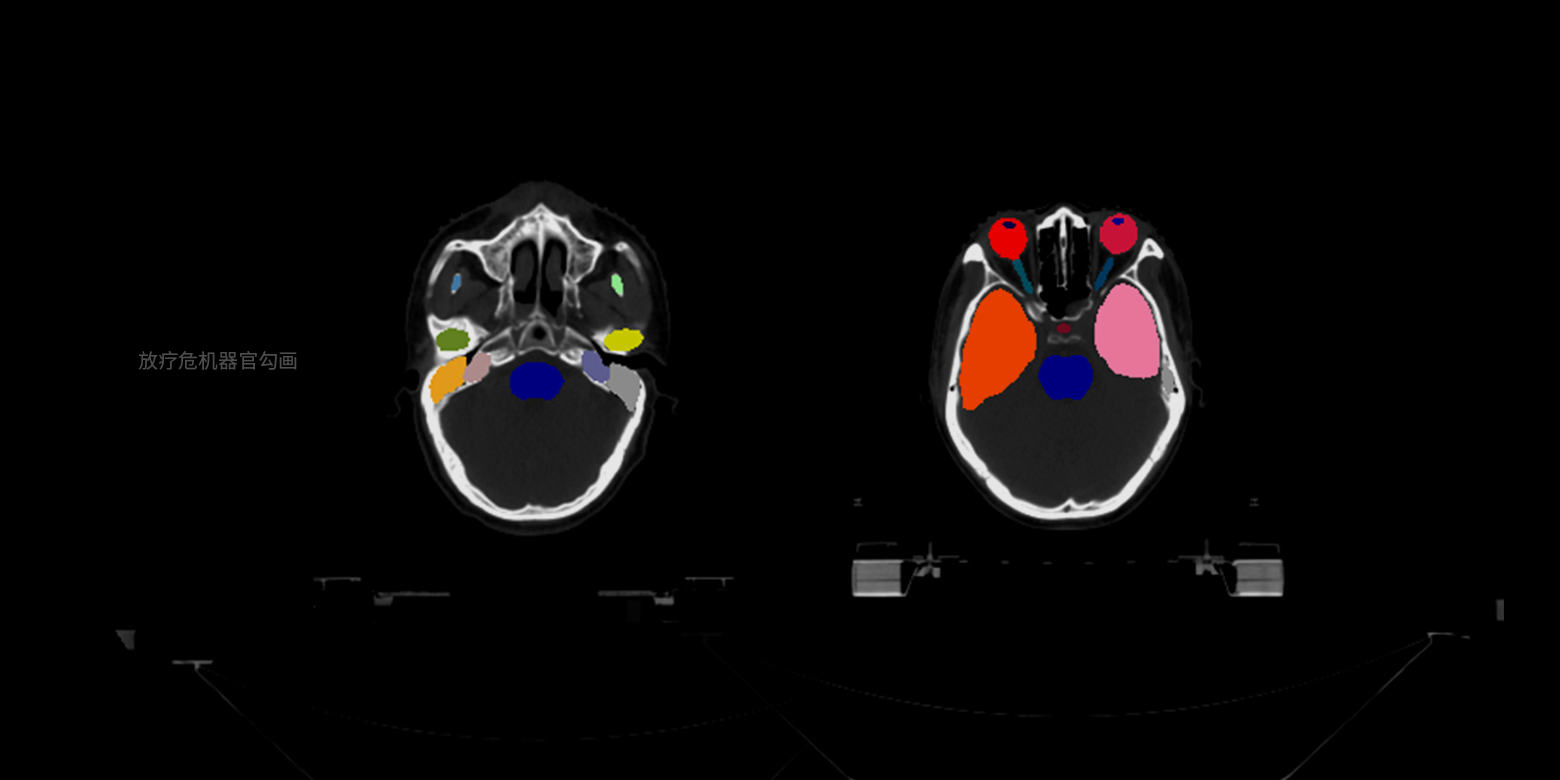

病灶部位的分割與量化

支持針對小樣本的醫學數據進行訓練,實現对多種器官病變提供像素級別的精確圖像分割,並能自動根據關鍵信息進行量化分析和診斷,例如幫助醫生節省人手勾畫放療靶區、分割骨盆腫瘤等,更好的利用時間規劃和為客戶定制化手術。